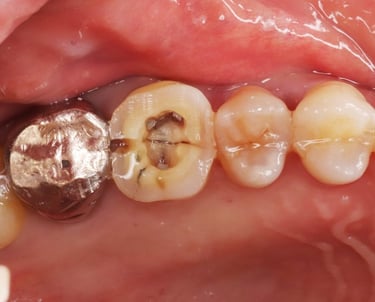

Se revisa si hay fracturas en la parte visible del diente. Las fracturas de la corona pueden ser causadas por trauma o caries extensas y pueden afectar el tratamiento endodóntico.

Evaluación de fracturas de la corona

Se analiza el estado de dientes que han recibido tratamientos endodónticos anteriores para verificar su éxito y determinar si se necesita un retratamiento.

Evaluación de dientes con tratamientos previos